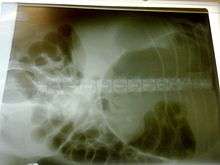

A diagnosis of gastric dilatation-volvulus is made by several factors. The breed and history will often give a significant suspicion of gastric dilatation-volvulus, and the physical exam will often reveal the telltale sign of a distended abdomen with abdominal tympany. Shock is diagnosed by the presence of pale mucous membranes with poor capillary refill, increased heart rate, and poor pulse quality. X-rays (usually taken after decompression of the stomach if the dog is unstable) will show a stomach distended with gas. The pylorus, which normally is ventral and to the right of the body of the stomach, will be cranial to the body of the stomach and left of the midline, often separated on the x-ray by soft tissue and giving the appearance of a separate gas filled pocket (double bubble sign).[17]